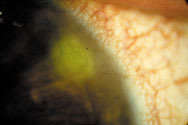

Figure 1. Contact lens peripheral

ulcer. |

Contact lens-induced peripheral ulcer CLPU (Figure 1) is a circular, well circumscribed, dense, yellowish-white, focal corneal infiltrate (0.2-2.0mm in diameter) with an overlying epithelial defect that stains with fluorescein, with diffuse infiltration of the surrounding stroma in its active stage. It is located in the peripheral to mid-peripheral cornea. CLPU is characterized by marked limbal and bulbar redness, usually localized to the quadrant adjacent to the lesion. Redness is the most common symptom reported by the patient, followed by pain or soreness, irritation or watering. CLPU is usually unilateral and typically features a single focal infiltrate; however, a number of infiltrates can occur, although this is rare. In severe cases, there may be mild anterior chamber involvement and photophobia. In mild cases, a patient may be asymptomatic and present to the clinic only with a scar as indication that an event occurred. CLPU can mimic early MK; however, CLPU symptoms are milder and begin to recede immediately on discontinuation of lens wear. The events usually resolve in a characteristic bulls-eye scar (Figure 2). The patients who present to our clinics with healed peripheral circular scars without treatment highlight the self-limiting nature of CLPU events.